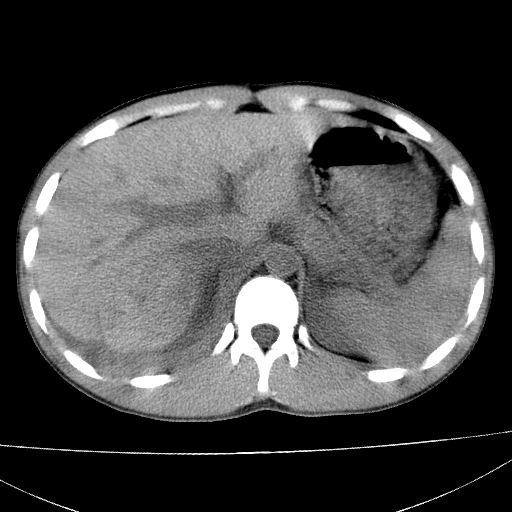

标题: CT15860:男,21岁,腹部外伤2小时伴胸疼。 [打印本页]

标题: CT15860:男,21岁,腹部外伤2小时伴胸疼。

肝脏及肾脏明显有损伤性改变并激发腹腔内积液(血),以肝脏撕裂及肾周积血显著。

1)肝破裂伴腹腔积液(血)。2)右肾破裂伴右肾包膜下及肾周血肿。3)腹部空腔脏器穿孔可能。4)右侧少量胸腔积液(血)。

1)肝破裂伴腹腔积液(血)。2)右肾破裂伴右肾包膜下及肾周血肿。3)右侧少量胸腔积液(血)。

肝肾挫裂伤,右肾周及包膜下血肿,腹腔积液,不排除空腔脏器穿孔,建议行增强检查

肝、右肾包膜下血肿,右侧腰大肌及腹膜后血肿;腹腔少量积血;腹腔疑有少量游离气体伴肠破裂。

肝右肾挫裂伤,右肾包膜下及肾周血肿.胸腹腔少量积液.脾脏下部密度稍不均,必要时,增强.

1肝挫伤伴腹腔积液。2右肾挫裂伤伴右肾包膜及肾后间隙肿血肿。3右肾脏周围的积气,十二指肠显示结构不清,考虑十二指肠降部破裂可能性大。